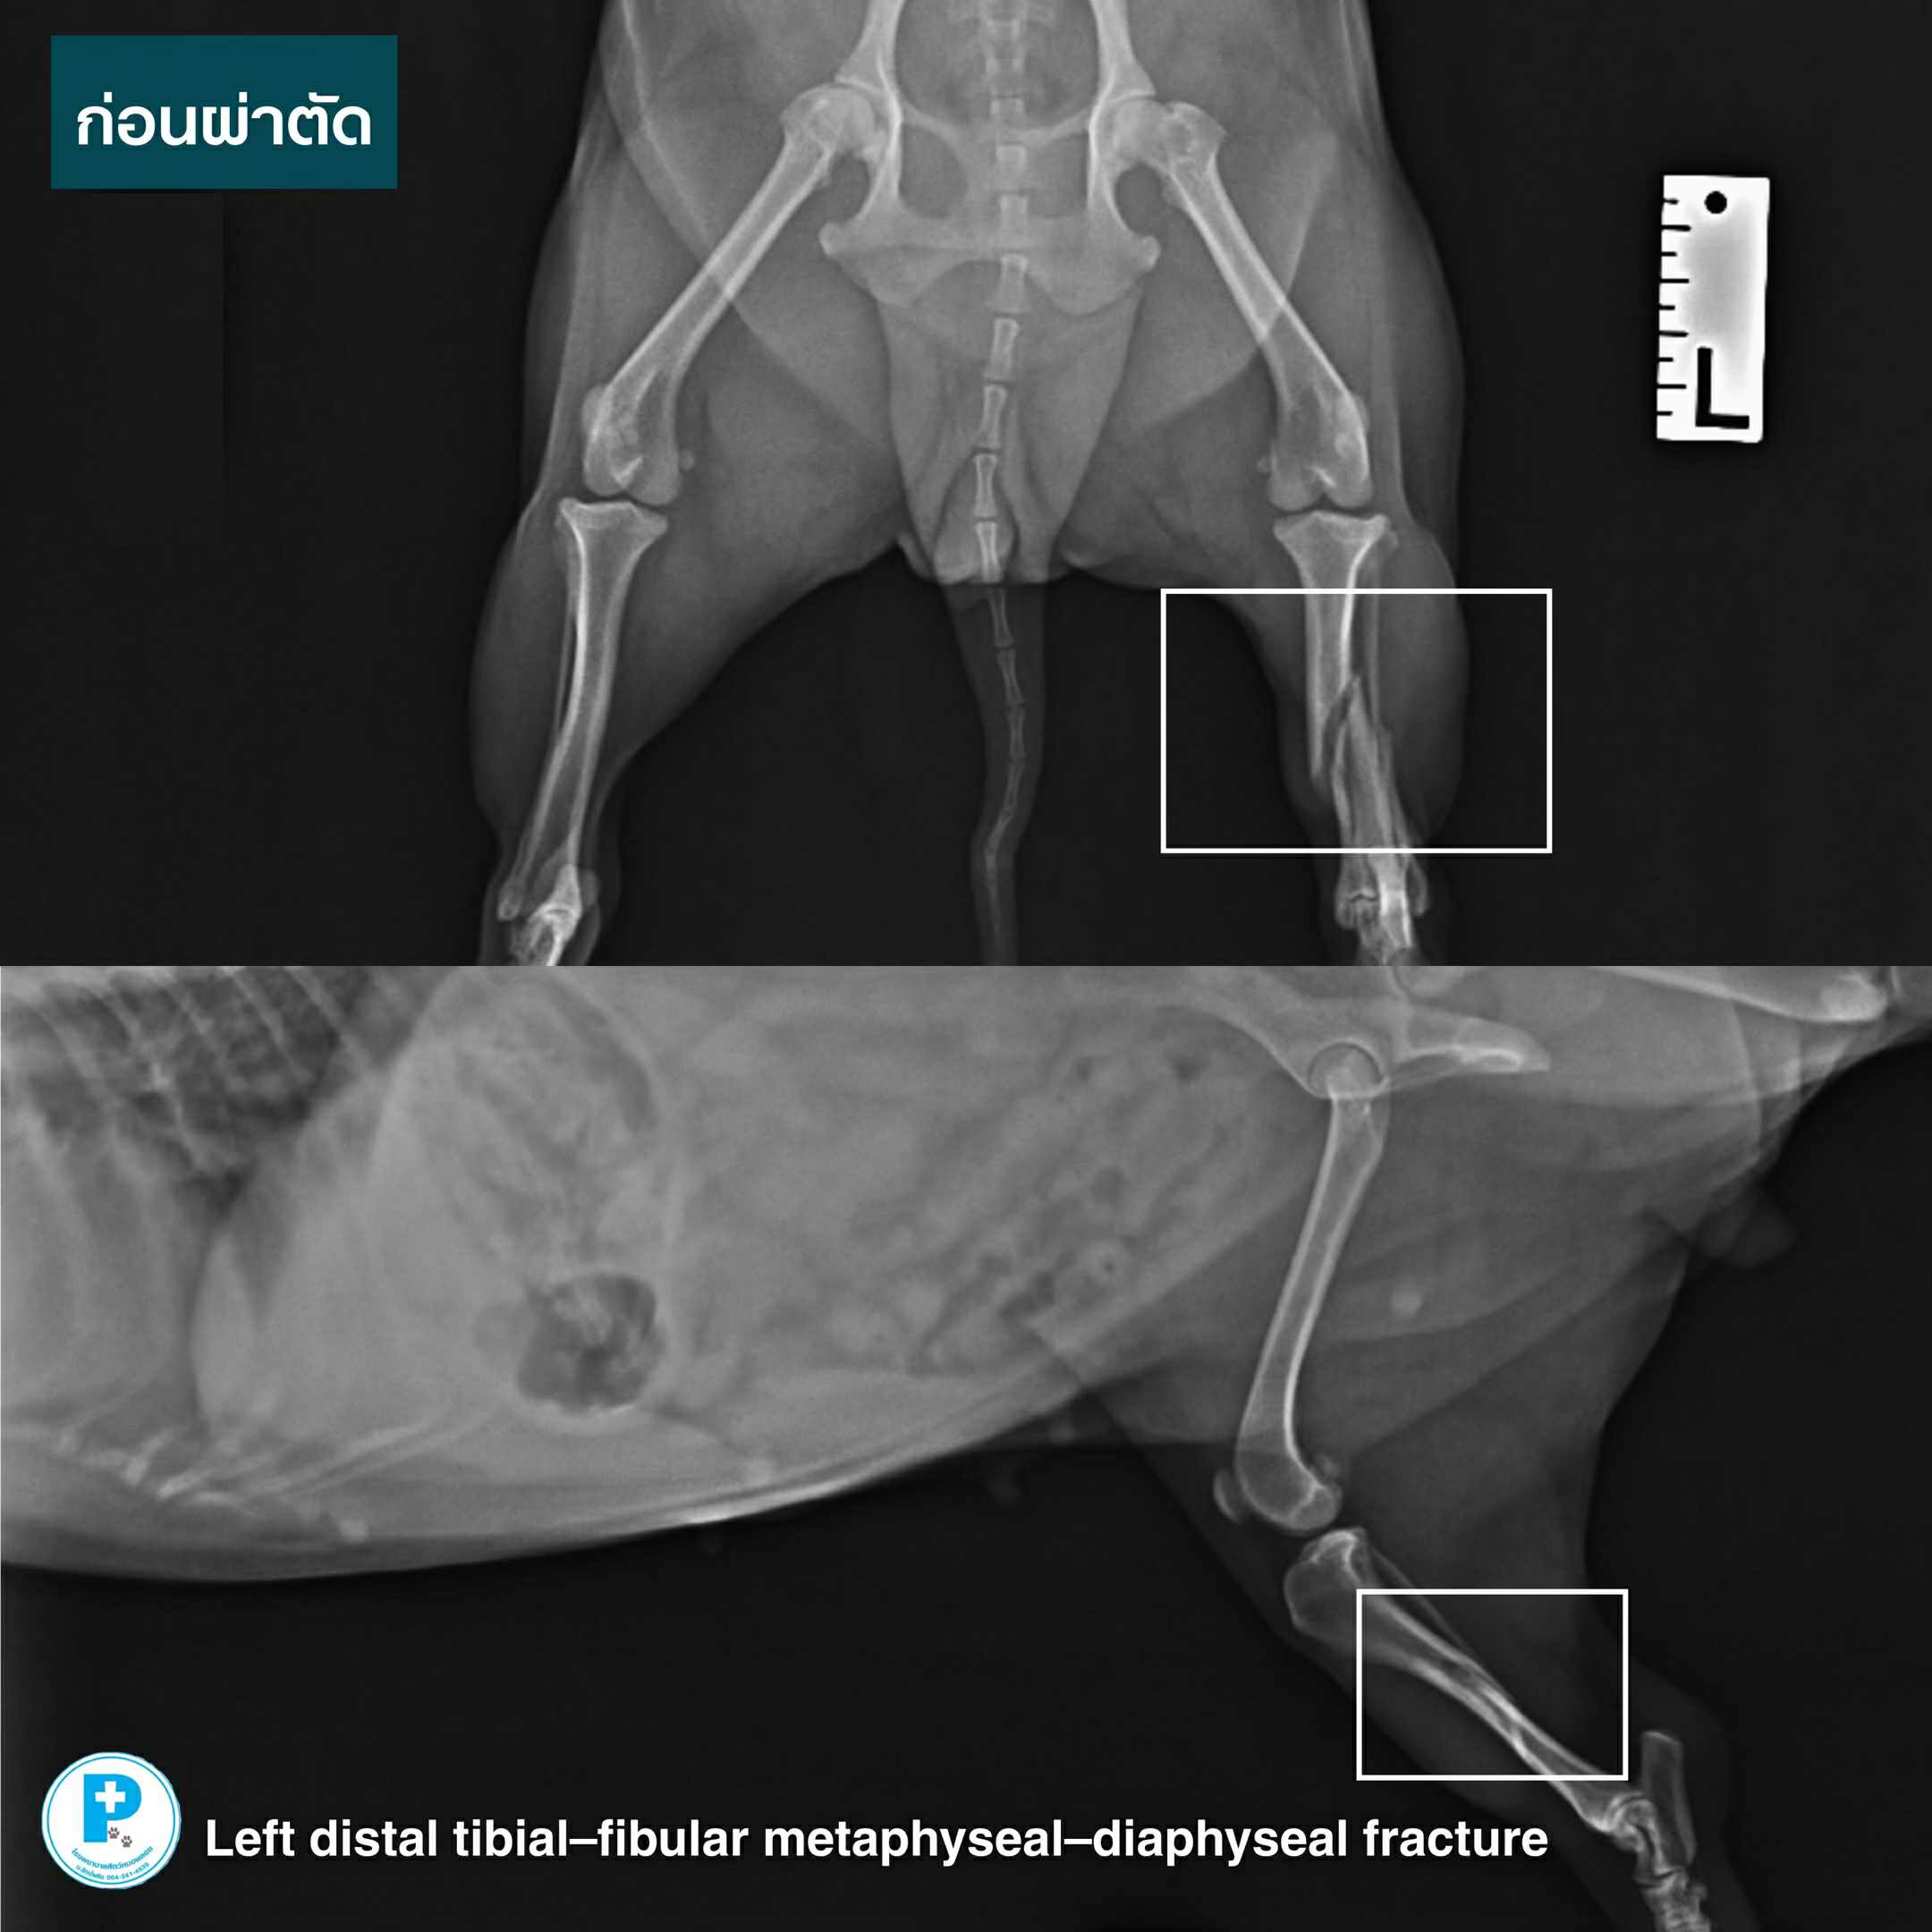

น้องมีตังค์ประสบอุบัติเหตุ กระดูกขาหลังซ้ายหัก Left distal tibial–fibular metaphyseal–diaphyseal fracture

ตำแหน่งนี้เป็นจุดที่กระดูกเลี้ยงตัวเองไม่ดี

หากรักษาไม่เหมาะสม มีโอกาส “ไม่ติด” และหักซ้ำได้สูง